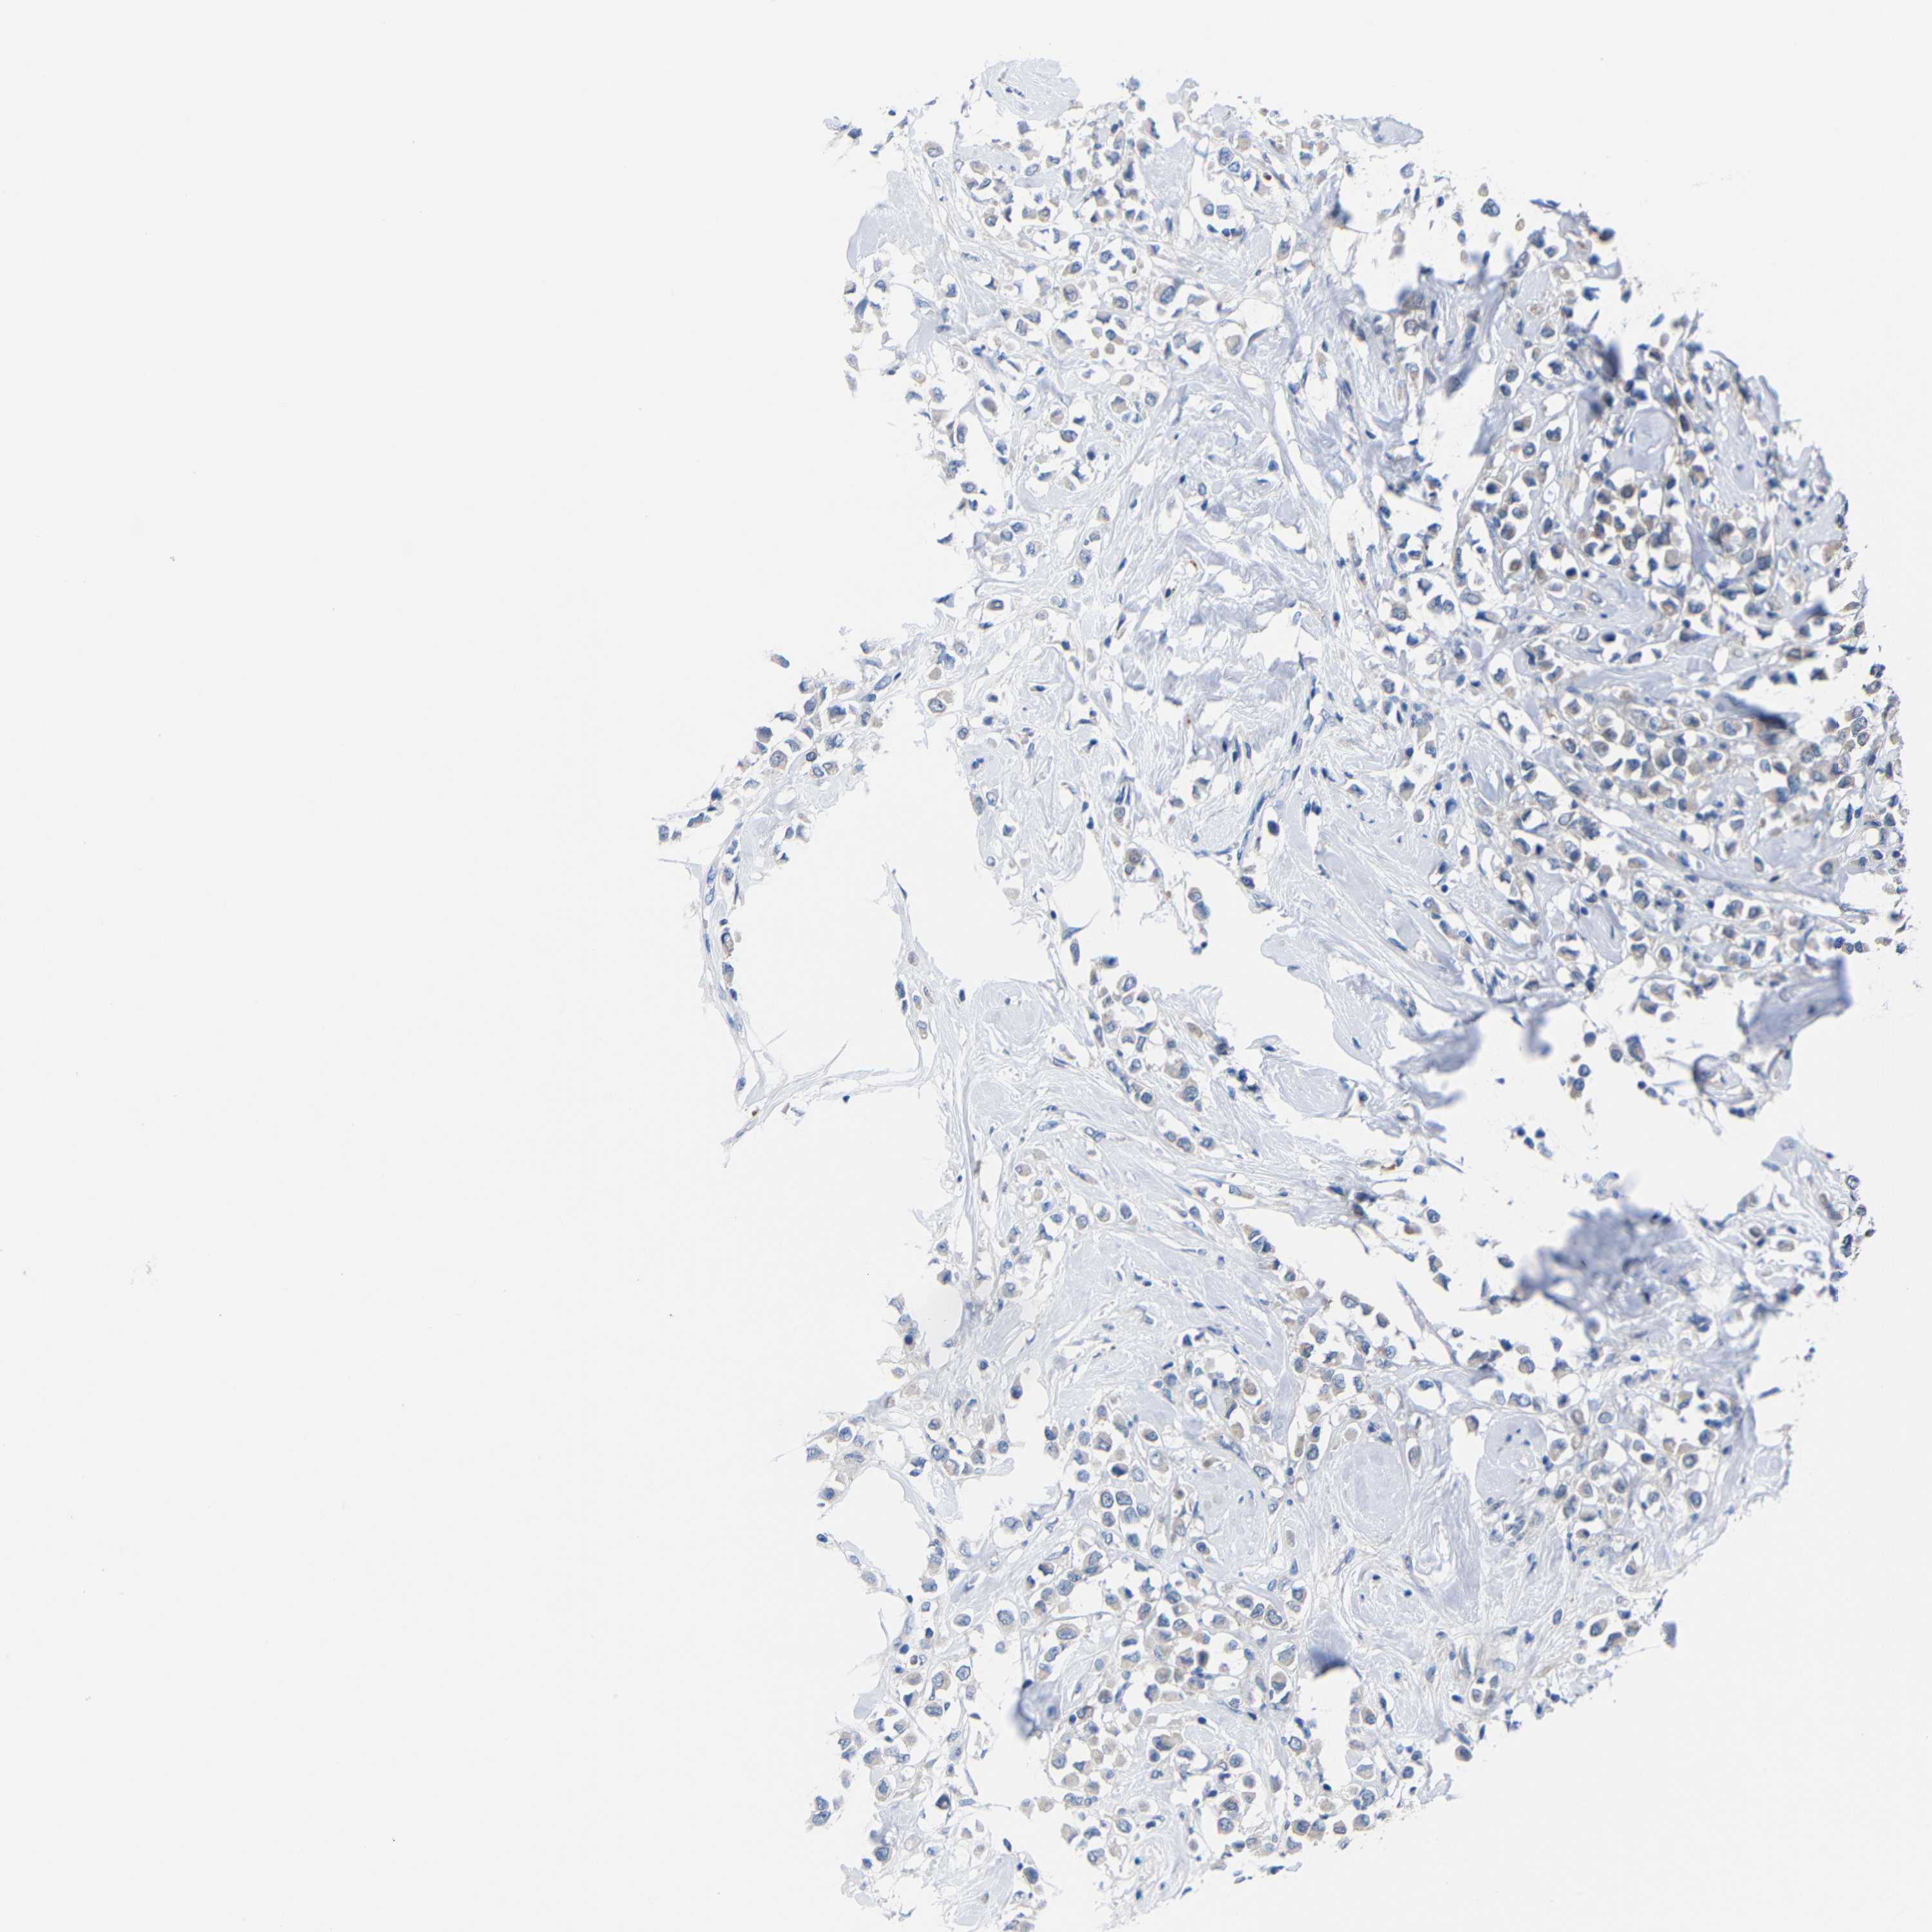

CANCER BREAST CANCER Show tissue menu

BRCA TCGA BRCA VALIDATION PROTEIN EXPRESSION

ANTIBODIES

AND

VALIDATION